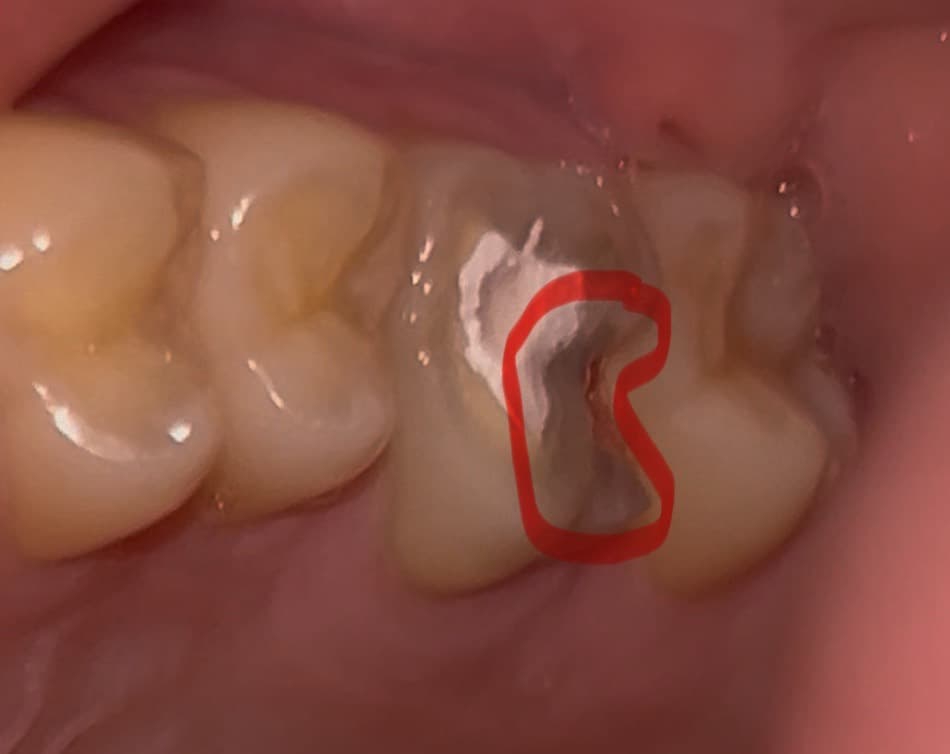

그런데 임시재료가 치아 전체가 아니고 부분만 채워졌어요;;; (신경치료 부분만 채워지고 깨진 이빨은 그대로)

또한 치아 모양을 봤을 때 제 잘못으로 재료가 탈락한 것인지, 그냥 덜 채워준 게 맞는 건지 알 수 있다면 알고싶습니다.

앞쪽에 하얀색 부분이 신경치료를 진행한곳입니다 저 뒷부분은 추후에 마무리 할때 단단한 재료로 채우고 크라운 치료를 합니다.

사진상으로는 덜 채워져있는 것이 아니라 치아에 구멍을 뚫은 만큼 잘 메워져있어보입니다.